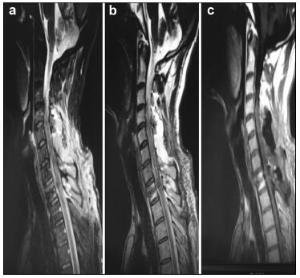

20170512093703  Figure 3 a–c. Preoperative MR images of Case 2.